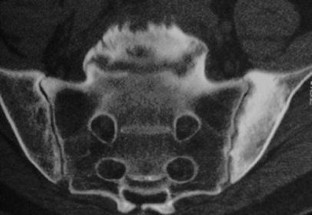

The SAPHO syndrome was a term coined to include a variety of musculoskeletal disorders associated with skin conditions, mainly palmoplantar pustulosis and acne conglobata. It is more correctly a spectrum which includes the following: skin lesions, osteoarticular manifestations of synovitis hyperostosis and osteitis affecting particular target sites, and·a clinical course marked by relapses and remissions. The major sites of involvement are the anterior chest wall, the spine, long bones, flat bones, and large and small joints. The distribution and severity of involvement varies from the adult to the pediatric form of chronic recurrent multifocal osteomyelitis (CRMO). The diagnosis of SAPHO syndrome is not difficult when the typical osteoarticular lesions are located in characteristic target sites. The diagnosis is more difficult if atypical sites are involved and there is no skin disease.

Fig. 4.